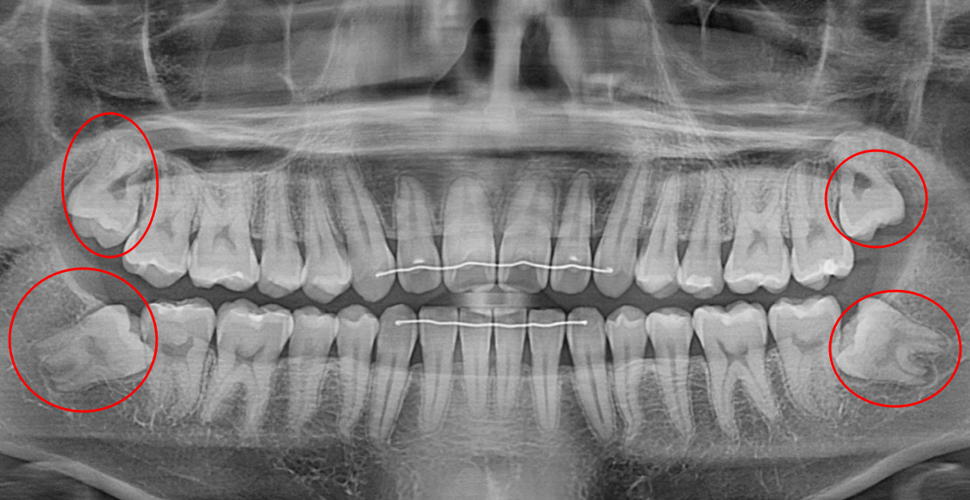

발치 전

사랑니 발치 후

20대 여성 환자분으로, 왼쪽 아래 사랑니 부위에 염증이 있는 상태로, 매복 사랑니의 뿌리 끝 부위가 심하게 휘고 신경까지 붙어 있는 상황이었습니다.

이런 케이스는 뿌리 끝까지 빼면서 신경까지 손상되는 위험성이 더 크기에 뿌리 일부를 남겨두는 것이 더 안전할 수 있습니다.

다행히 신경 손상 없이 뿌리 모두 안전하게 발치하였습니다.